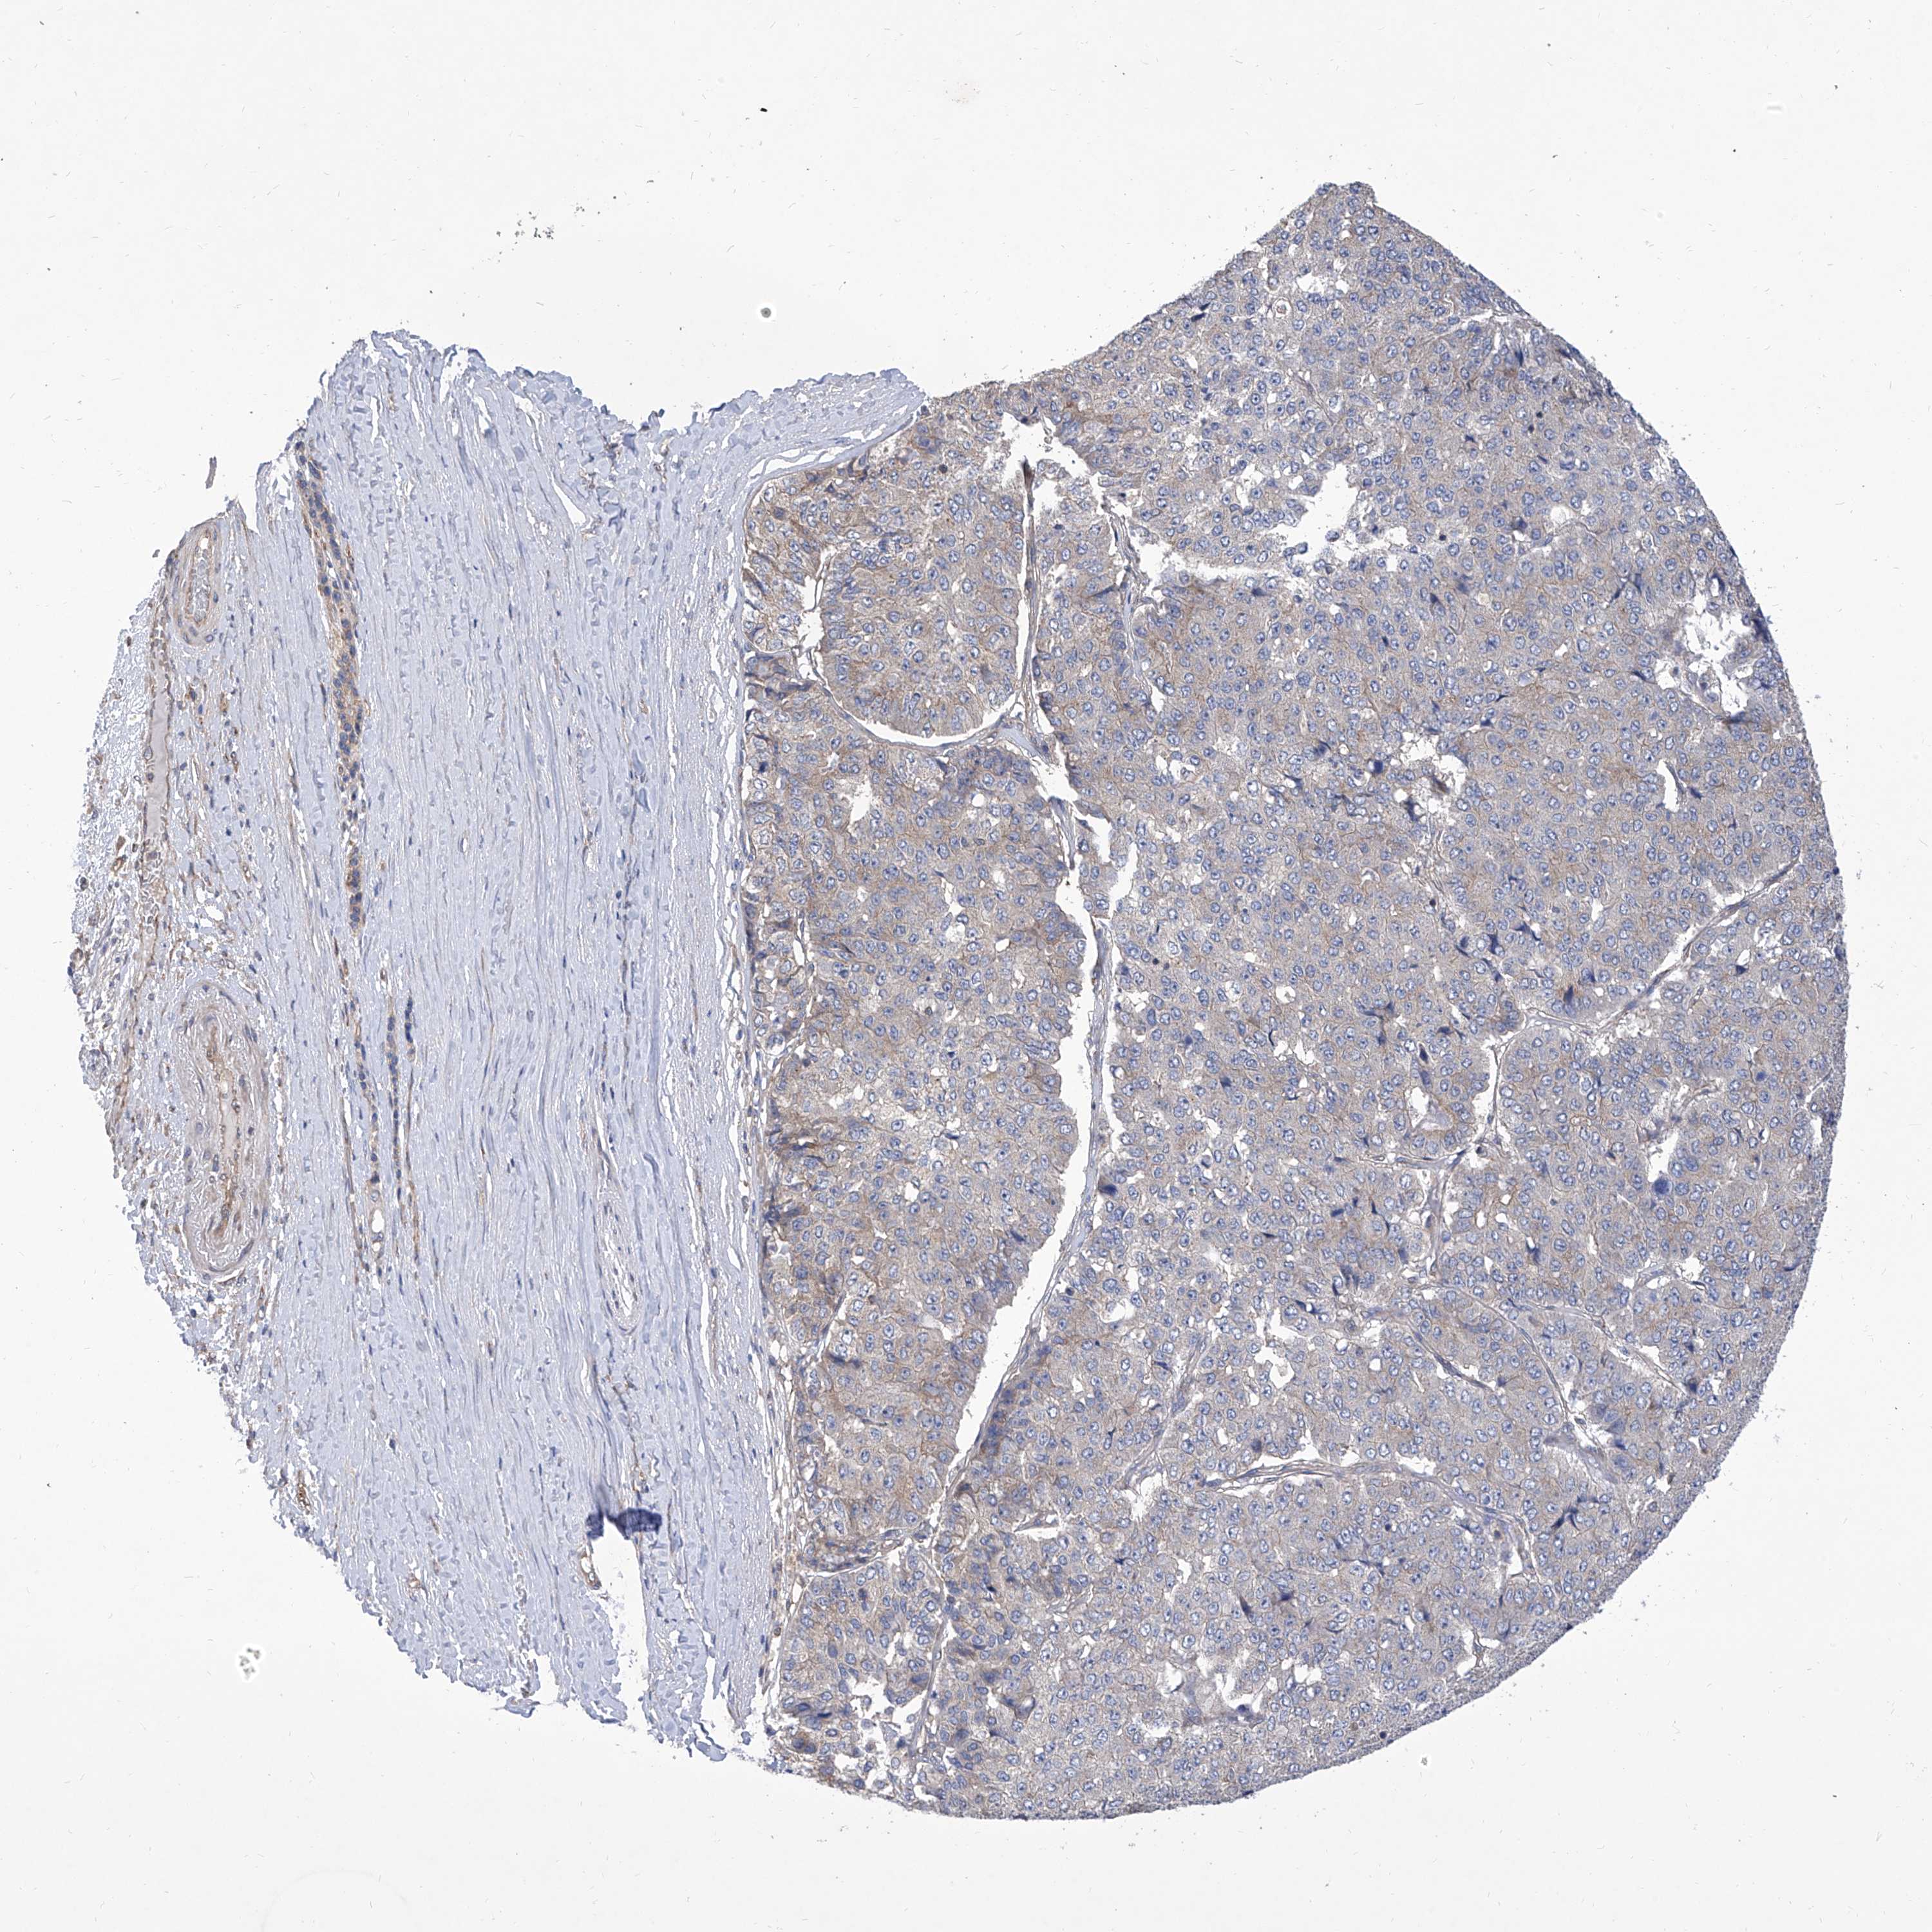

PANCREATIC CANCER - Protein expressioni

A mouse-over function shows sample information and annotation data. Click on an image to view it in a full screen mode. Samples can be filtered based on level of antibody staining by selecting one or several of the following categories: high, medium, low and not detected. The assay and annotation is described here.

Note that samples used for immunohistochemistry by the Human Protein Atlas do not correspond to samples in the TCGA dataset.

Antibody stainingi

Antibody staining in the annotated cell types in the current human tissue is reported as not detected, low, medium, or high, based on conventional immunohistochemistry profiling in selected tissues. This score is based on the combination of the staining intensity and fraction of stained cells.

Each image is clickable and will lead to virtual microscopy that enables deeper exploration of all samples and also displays staining intensity scores, fraction scores and subcellular localization as well as patient and tissue information for each sample.

Antibody HPA030164

Antibody HPA030165

Antibody HPA030166

Adenocarcinoma, NOS